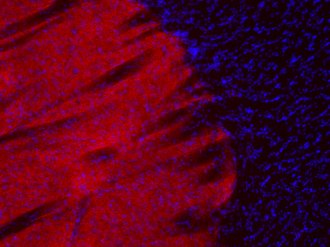

ICC: 1 : 500 gallery

IHC: 1 : 500 gallery

Immunocytochemistry (ICC) on 4% PFA fixed cells. Immunoreactivity is usually revealed by fluorescence. Some antibodies require special fixation methods. For details, please refer to the “Remarks” section.

Immunohistochemistry (IHC) on 4% PFA perfusion fixed tissue with 24h PFA post fixation. Immunoreactivity is usually revealed by fluorescence or a chromogenic substrate. Some antibodies require special fixation methods or antigen retrieval steps. For details, please refer to the ”Remarks” section.